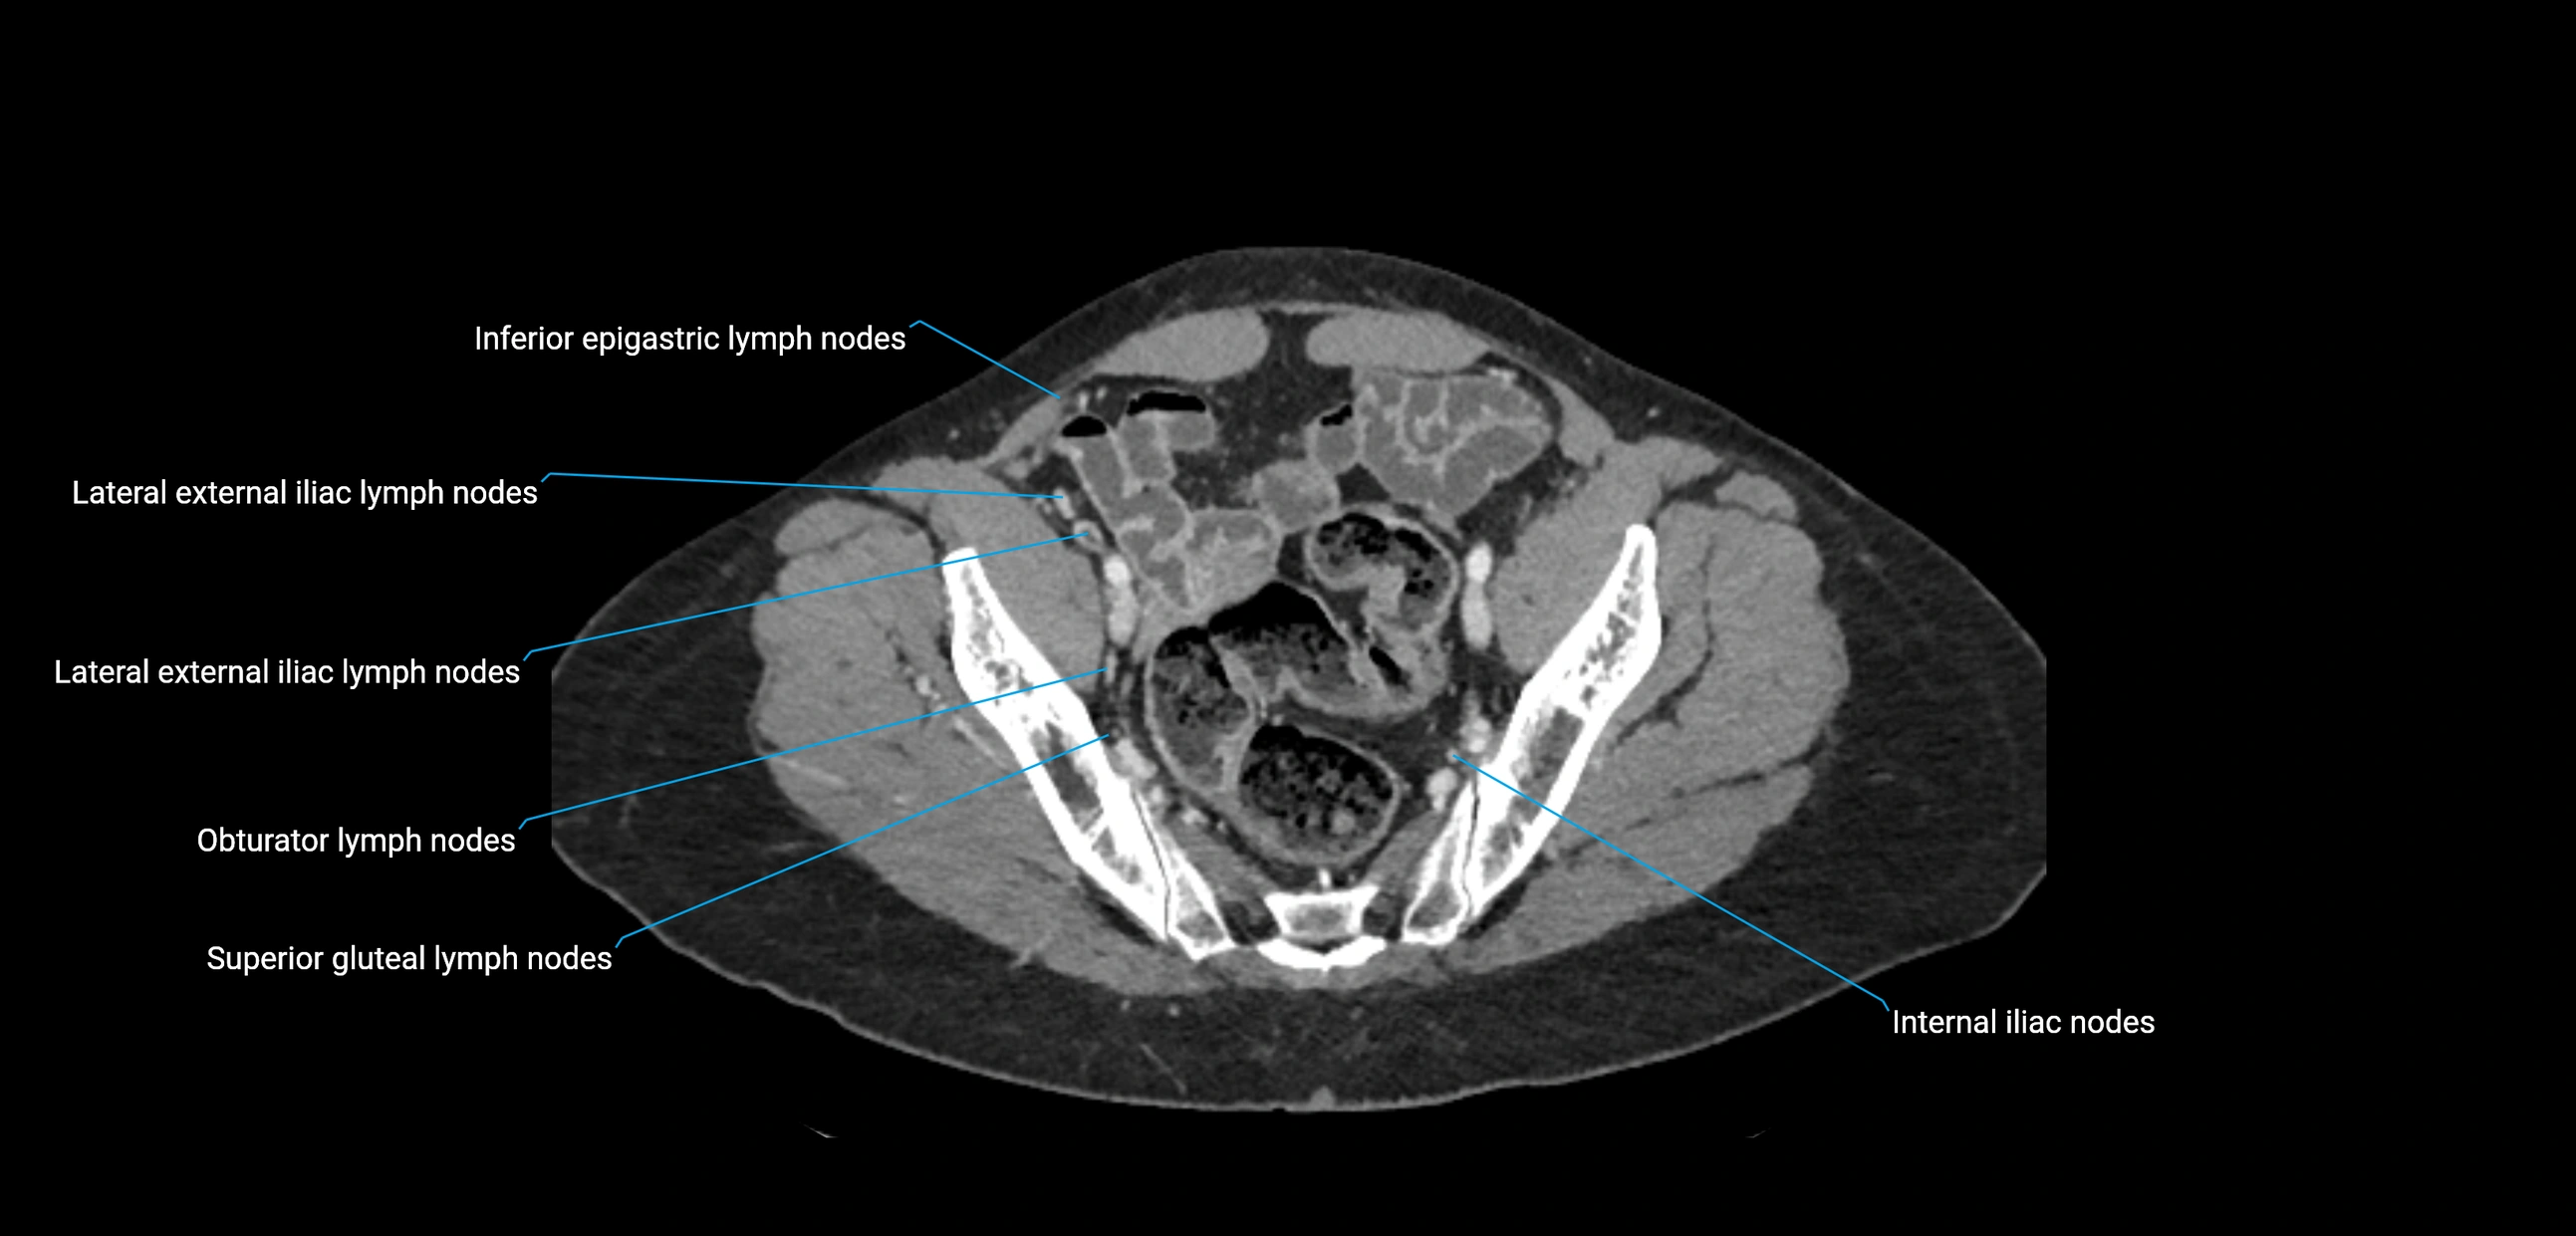

CT image

image

CT Appearance

CT Pre-Contrast:

• Nodes appear as soft-tissue density nodules adjacent to the aorta and IVC

• Calcification may be seen in chronic infections (e.g., tuberculosis)

CT Post-Contrast:

• Normal nodes enhance homogeneously

• Malignant nodes may show heterogeneous enhancement, central necrosis, or conglomerate formation

• Size >1 cm short axis is suspicious, though morphology and distribution are equally important